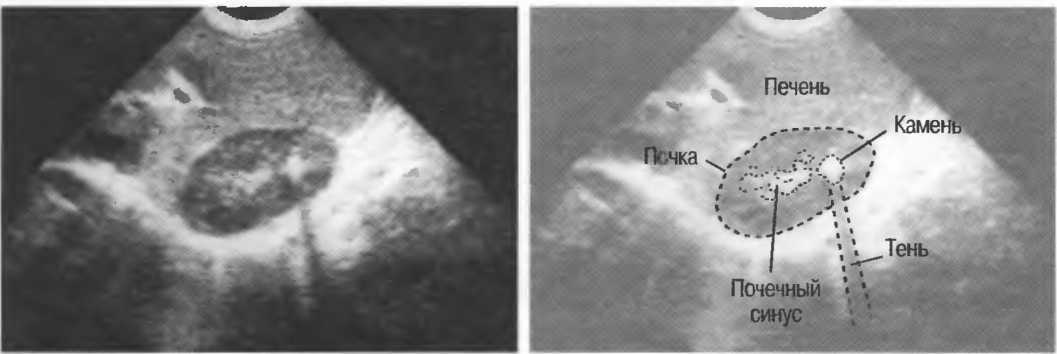

Тени

Кости, камни и кальцинаты дают акустическую тень. Ультразвук не может проходить через кость, если она только не очень тонкая (как, например, кости черепа у новорожденного). При необходимости рассмотреть структуры, расположенные глубже, необходимо использовать различные углы наклона датчика (рис. 17а,б).

Рис. 17а. Большая акустическая тень за камнем в желчном пузыре.